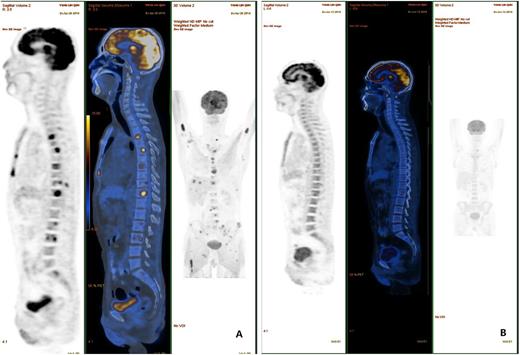

Figure 1. Comparison of pre-treatment and post-treatment PET-CT scan in one relapsed/refractory DLBCL patient.